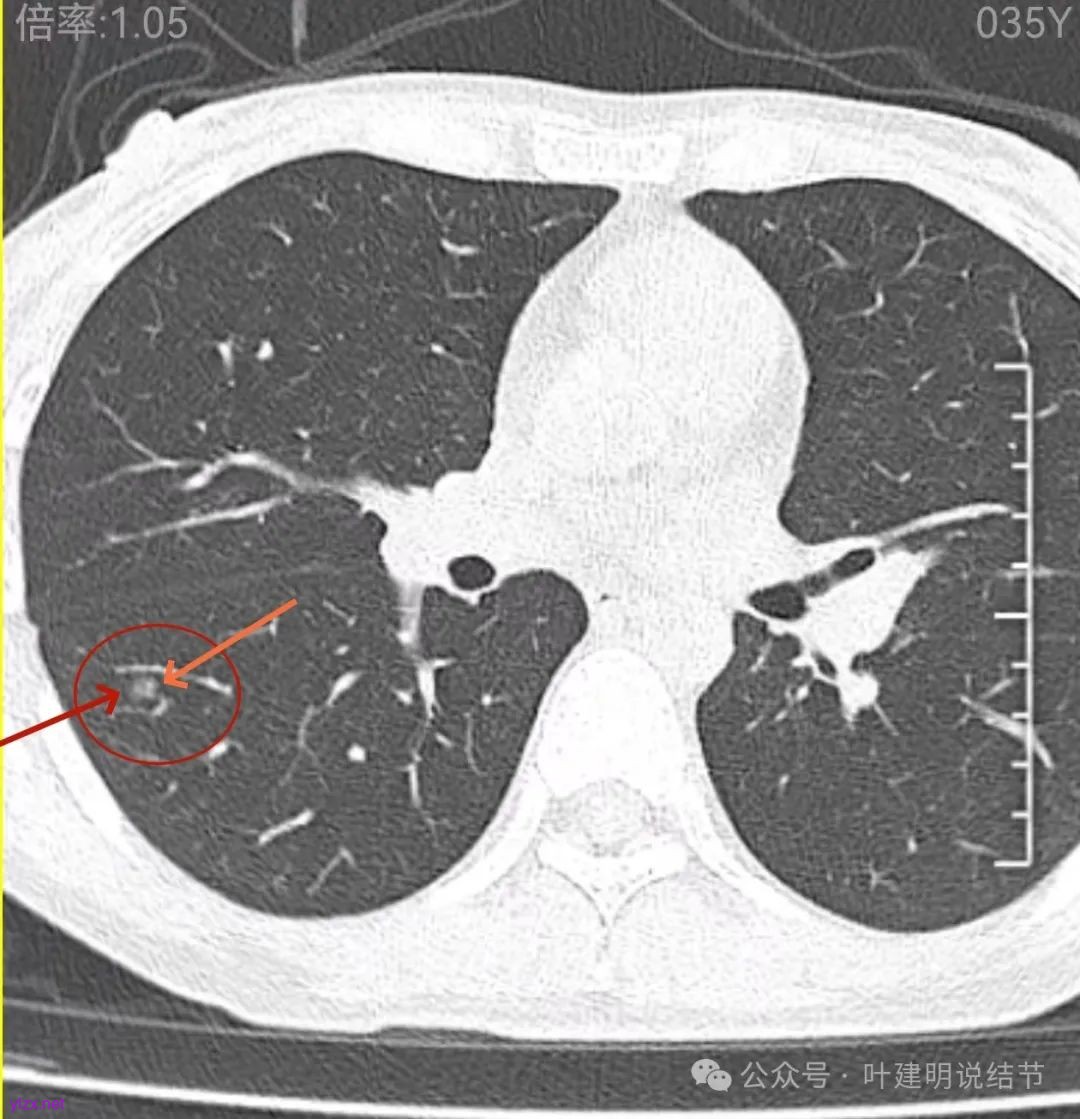

再看2022年9月的影像:

密度甚高,边界与轮廓清楚,只看这真的不像恶性些。

边缘区也瘤肺界限稍糊,整体轮廓还行。有进展的是不是就是淡磨那处?

两肺多发结节,左侧黄色标注的考虑是肺泡上皮增生可能性大;蓝色的考虑肺泡上皮增生或者少许慢性炎可能性大;右侧红色宽起来并带有红色箭头的这处是主病灶,偏混合密度,整体轮廓较为清楚,边缘显得毛糙,从2024年12月份的来看,要考虑是肿瘤范畴,原位癌或者微浸润性腺癌可能性较大,也不能完全排除不典型增生。但是在2022年的时候,这个病灶的边上也有一个实性的微小结节,如果只看2022年的,这么小的实性结节,又比较圆,表面也显得较为光滑,是要考虑良性的,当然太小了需要动态观察。回头再重新来看2024年底的,发现绿色箭头所指的这个微小实性的较2022年几乎没有变,去仔细寻找2022年的,发现当时在实性结节旁边也有密度很淡的一点磨玻璃影(也可能真的就是一处,只是扫描不够薄,密度的变化有些突兀而已),而到了2024年12月份,实性微小这处没有明显变化,但是原来很淡的磨玻璃变成了混合磨玻璃,范围也明显扩大。所以总体来看右肺下叶这处是考虑恶性的,而且从磨玻璃结节角度来讲,还是生长比较快的,就是说还是有一定风险的。加上左侧还有两处也是磨玻璃持续存在,虽然边缘轮廓显模糊一点,但多年以后也可能仍然要变成原位癌或者微浸润性腺癌之类的东西。通盘考虑以后,我倾向于右侧近期单孔胸腔镜下微创局部切除,左侧随访观察,等到有进展并风险增加再来考虑处理。意见供参考!